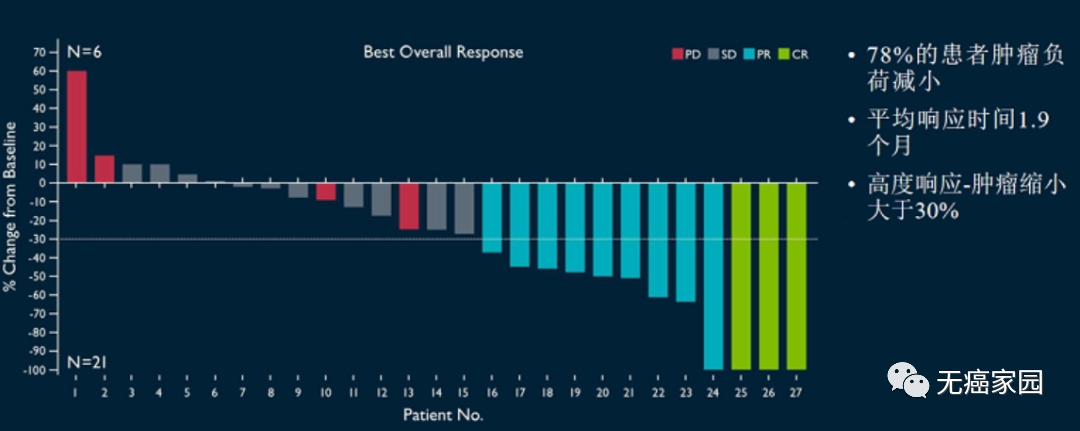

疾病控制率89%!LN-145疗法获FDA突破性疗法称号!

2019年6月,FDA批准肿瘤浸润淋巴细胞(TIL)治疗方法LN-145为突破性的治疗指定,这是用于实体瘤的细胞免疫疗法首次获此殊荣,相信距离上市也仅是时间问题,一旦FDA批准,这将是首款用于实体瘤的细胞免疫疗法,将给癌症患者带来巨大的生存获益。

FDA此次授予是基于正在进行的第二阶段innovaTIL-04(C-145-04)积极的试验的数据,摘要数据显示,晚期宫颈癌患者的TIL治疗总体反应率(ORR)为44%。

在2019年2月4日的数据截止时,有27名可评估的患者。

结果显示:

1、44%(12名)的患者有效果,包括1名完全应答,9名部分应答和2个未确认的部分应答;

2、疾病控制率为89%;

3、中位随访时间为3.5个月,12例患者中有11例持续应答;

4、没有任何严重的副作用发生。

5、疾病控制率89%!首个迎战实体瘤的细胞免疫疗法获FDA突破性疗法称号!